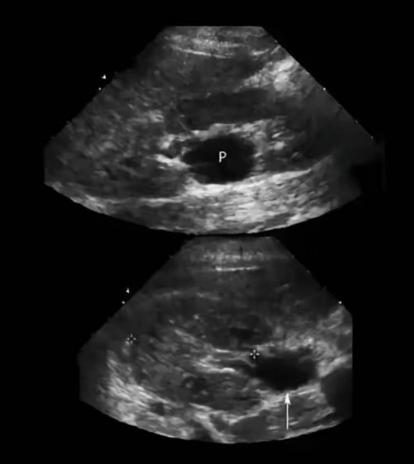

辽宁一59岁女子去医院取避孕环,几年后,她用手机播放歌曲时,发现医生悄悄在她子宫里安了监听器,导致她肚子很难受,女子一气之下,把医院告上法庭... 没人能想到,一次常规小手术,竟牵扯出医患信任与医疗安全的双重拷问。 午后的社区诊所里,叶女士正拿着超声报告,眉头紧锁一言不发。 这是她术后第八次做检查,结果依旧和之前一样,无任何异常。 可她下意识按住下腹,那种莫名的牵拉感,仍时不时浮现。 “肯定有东西在里面,不然我不会一直不舒服。”她喃喃自语。 这份固执的怀疑,要从半年前那场取环手术说起,也关乎医疗安全的底线。 医疗安全从来不是一句口号,而是藏在每一次术前准备、术中操作里。 当初叶女士选择这家医院,就是看中其口碑和规范的诊疗流程。 术前,护士反复核对她的信息,医生详细告知手术细节和注意事项。 她记得自己还特意问过,会不会有异物残留,医生笑着摇头否认。 那时的她,从未想过,这场十几分钟的小手术,会改变她的生活。 手术当天很顺利,走出手术室时,她甚至觉得自己多虑了。 可术后第三天,下腹胀痛开始加剧,还伴随着低烧,浑身乏力。 她第一时间联系主治医生,对方说这是术后正常反应,让她按时服药。 可服药一周,不适非但没减轻,反而多了种奇怪的“异物感”。 真正让她陷入恐慌的,是一次偶然的手机放歌经历。 她坐在沙发上听歌,手机靠近腹部时,突然感到一阵轻微拉扯。 这个瞬间,一个荒谬却又让她坚信的念头冒了出来:被植入了监听器。 她连夜翻出手术相关的所有单据,反复查看,越看越觉得不对劲。 她想起手术时,医生曾离开过几分钟,怀疑就是那段时间做了手脚。 越想越焦虑的叶女士,第二天一早就带着单据,去医院讨要说法。 医院工作人员耐心接待了她,调取了手术监控和完整病历。 监控清晰显示,手术全程规范,医生离岗是去取必要的手术器械。 主治医生再次为她解释,取环手术无需任何电子设备,不可能植入异物。 可叶女士根本听不进去,她觉得医院是在刻意隐瞒,逃避责任。 医疗安全的维系,不仅需要医院的规范操作,也需要医患间的基本信任。 协商无果后,叶女士下定决心,一纸诉状将医院告上了法庭。 她的诉求很简单:取出体内“监听器”,赔偿自己的身心损失。 这场离奇的诉讼,很快在当地传开,引发了不同的声音。 有人觉得她小题大做、胡思乱想,也有人心疼她术后的痛苦与焦虑。 法院开庭审理时,医院提交了全套诊疗记录、监控录像和专家证言。 多位妇科专家当庭说明,术后囊性回声是常见现象,与异物无关。 为了让叶女士信服,法院还特意委托第三方机构,为她做了专项检查。 检查结果依旧显示,其腹部无任何金属、电子设备或异物残留。 即便证据确凿,叶女士依旧不肯相信,坚持自己的感受没有错。 最终,法院因叶女士举证不足,依法驳回了她的诉讼请求。 判决下来后,医院并没有置之不理,而是主动联系叶女士提供帮助。 安排心理医生为她疏导,邀请妇科专家为她制定后续调理方案。 医院的做法,恰恰体现了医疗安全的延伸——术后关怀与人文关怀。 其实,类似叶女士的情况,在临床中并不少见,只是表现形式不同。 很多患者术后出现不明不适,检查却无异常,容易陷入自我怀疑。 这背后,是躯体形式障碍的困扰,也是医疗服务中容易忽视的痛点。 如今,叶女士的状态有了明显好转。 她依旧会定期去医院复查,但不再执着于“监听器”的猜测。 在心理医生的疏导和妇科专家的调理下,她的下腹不适渐渐减轻。 她开始尝试放下焦虑,慢慢回归正常的生活,按时作息、规律饮食。 偶尔想起这场风波,她也会感慨,当初不该被极端想法冲昏头脑。 而这起案例,也给所有医疗机构和从业者敲响了警钟。 医疗安全无小事,每一次沟通、每一次操作,都关乎患者的信任与安危。 唯有坚守规范、秉持人文关怀,才能化解医患矛盾,守护好每一位患者。 信源:果然新闻